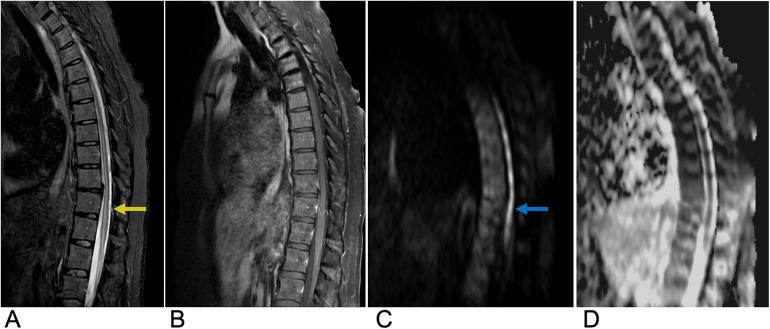

Spinal lesions encompass a diverse range of pathologies, including primary and secondary tumors, infectious processes, vascular malformations, traumatic injuries, and degenerative conditions, each with distinct imaging characteristics crucial for accurate diagnosis and management. Imaging plays vital roles in assessing lesion morphology, anatomical localization, and neurological impact, guiding clinical decision-making and therapeutic planning. This review systematically explores spinal lesions based on their anatomical compartments, highlighting key radiological features and providing a comprehensive reference for radiologists.